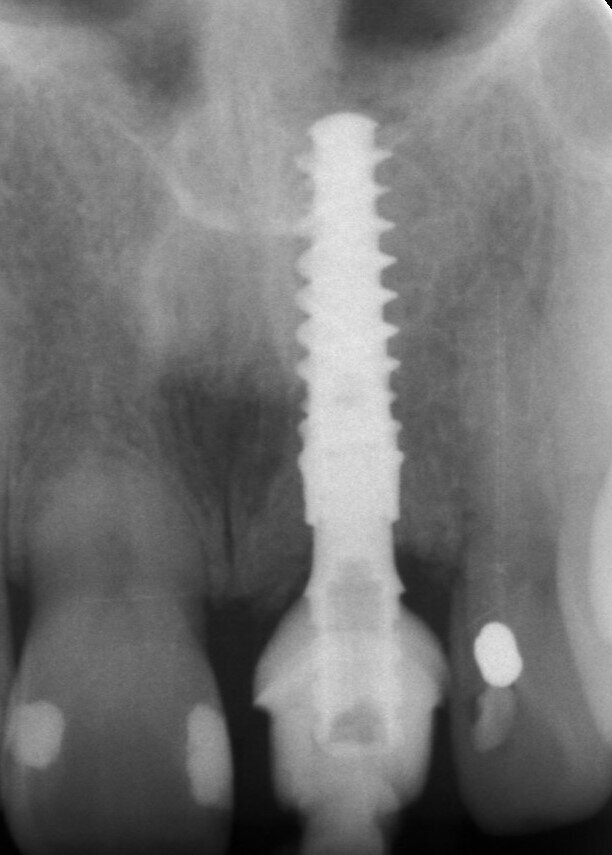

A 53-year-old female patient presented to the office with a fractured left central incisor which had been repeatedly bonded to a ceramic crown (Figs. 1 & 2). Anamneses and examination established good systemic and oral health, a well-balanced occlusion and no smoking habits. Cone beam computed tomography (CBCT) and a periapical radiograph showed external root resorption with very limited insertion into the alveolar bone, insufficient for adequate conventional intra-radicular post placement (Figs. 3 & 4). Considering that the fractured tooth was in the aesthetic zone, the patient requested restoration in the safest and fastest way possible.

Fig. 3: Pre-op periapical radiograph.

Fig. 29: Periapical radiograph one week post-op.

Fig. 33: Final result radiograph.

The final prosthesis was designed using Straumann CARES Visual following a digital workflow. During the design step, it was possible to see that the screw access hole would stay completely to the palatal side with no interference in the aesthetics of the restoration. A monolithic ceramic crown (Prettau Zirconia, Zirkonzahn) was milled and cemented extra-orally to a regular base/wide base Variobase (Straumann) with a gingival height of 1.5 mm, corresponding to the healing remodelling of the bone architecture (Fig. 30). The restoration was seated and screwed to a torque of 25 Ncm after occlusion, contact points and excursive movements had been checked (Figs. 31–33).